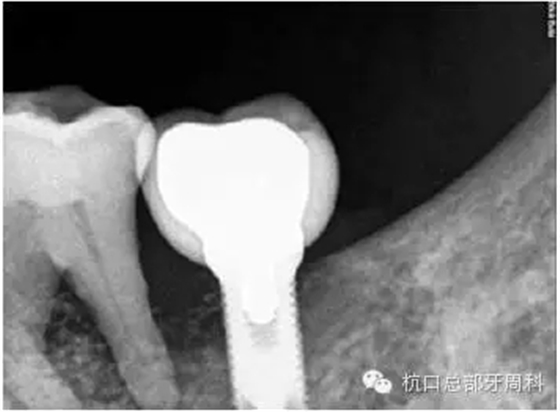

全景片:大范圍火山口樣/彈坑樣骨缺損

CT:左下缺牙區(qū)及部分升支存在骨破壞

初診時全景片2011.7